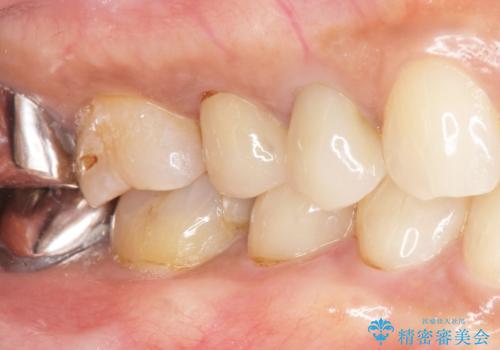

歯が欠けて舌が引っかかる セラミックインレー 50代女性

- 歯が欠けて舌が引っかかることを主訴に来院された患者様です。

精査したところ、右下小臼歯(右下4)が欠けていました。

古いレジンを取り除いてしっかり治療したいという患者様のご希望により、セラミックインレーによる修復を行いました。

自然な仕上がりと咬み心地に喜んで頂けました。

インレーの種類:e-max press セラミックインレー